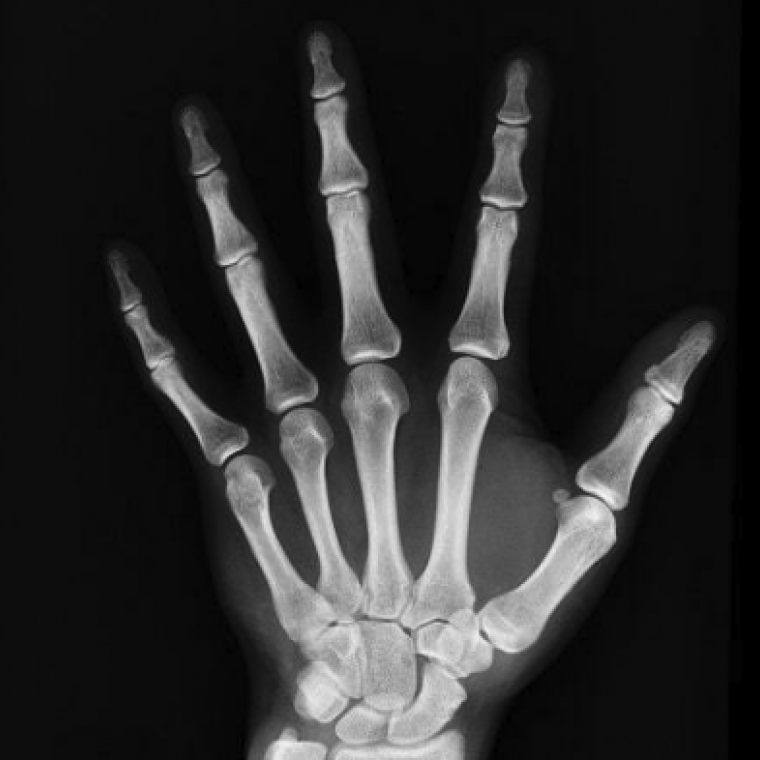

Fraxpert is an AI-supported fracture diagnostic system to deliver fast and accurate plain film interpretation. Radiologists and A&E clinicians are exhausted and overworked. Fraxpert aims to bridge the gap between supply and demand for image diagnostic interpretation, so that patients receive their correct diagnosis at the first point of consultation and radiologists never have to work outside their contracting hours.

Confident Fracture Detection

Fraxpert aims to support radiologists and frontline clinicians by confidently confirming the presence or absence of fractures in x-ray images, the same way as expert radiologists.